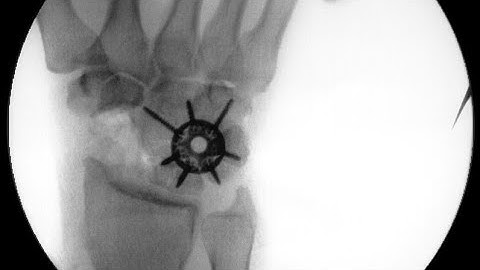

How not to miss Acute Scaphoid fracture - Management principles - Dr. Anil Bhat